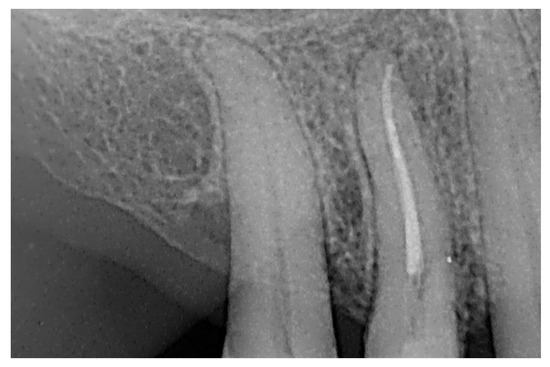

At the 12-month radiographic follow-up, healing of the EPL was confirmed. Restoration of the lamina dura and the periodontal ligament adjacent to the treated site was observed (Figure 16 and Figure 17).

Figure 16.

Intraoral radiography of tooth 1.4 at 12-month follow-up.

Figure 17.

EPL before (A) and after treatment (red circle showing mesiocervical widening of the lamina dura space) (B) and at 12-month follow-up (C) with radiographic evidence of restoration of the lamina dura (green circle), periodontal ligament space and absence of PL.

In the present case report, a one-year follow-up is presented, demonstrating excellent progression of lesion healing, an increase in the height of the alveolar bone adjacent to the lamina dura, resolution of the pathological probing depth, recovery of the continuity of the periodontal ligament and lamina dura along the root surface and in correspondence with the previously affected area of the cervical resorption and lesion, and complete remission of odontogenic symptoms, restoring the functional integrity of the tooth [33]. Consequently, the efficacy of the treatment can be affirmed: through the use of bioceramic cements in two formulations and the implementation of a meticulously performed intraoperative endodontic technique, a successful therapeutic outcome was achieved, with the dental element remaining functional and in position within the arch.